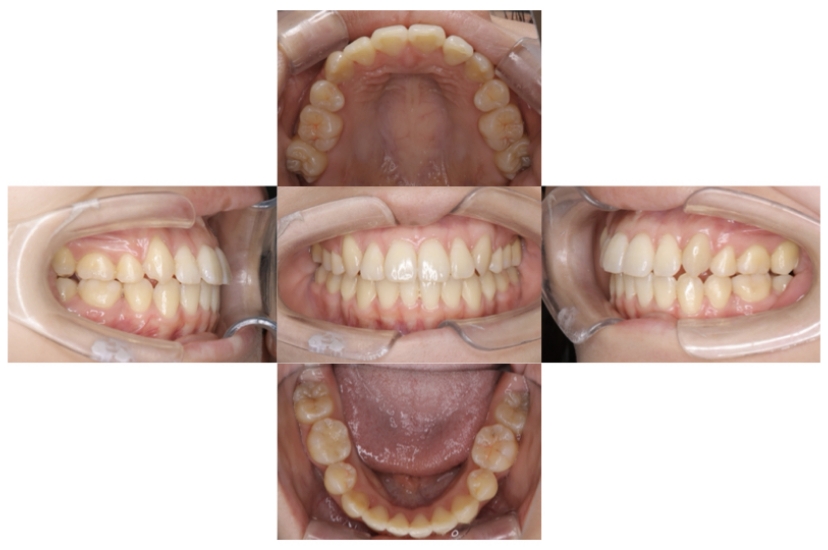

上下顎叢生(上下の前歯のガタガタ)のケースです。

装置はラビアル(上下表側)で、上下顎の小臼歯を4本抜歯を行っています。抜歯したスペースを使って、上下の前歯の後方移動と叢生(ガタガタ)の改善を行っています。

主訴 歯並びが悪く、舌を噛んでしまうのを治したい。

年齢・性別 27歳 男性

お住まいの地域 東京都大田区

治療方針 抜歯スペースを利用して上下前歯の叢生(ガタガタ)の改善

抜歯部位 上下顎左右第一小臼歯

使用装置 ラビアル(上下表側)、顎間ゴム

治療期間 3年1か月

治療回数 30回

BEFORE